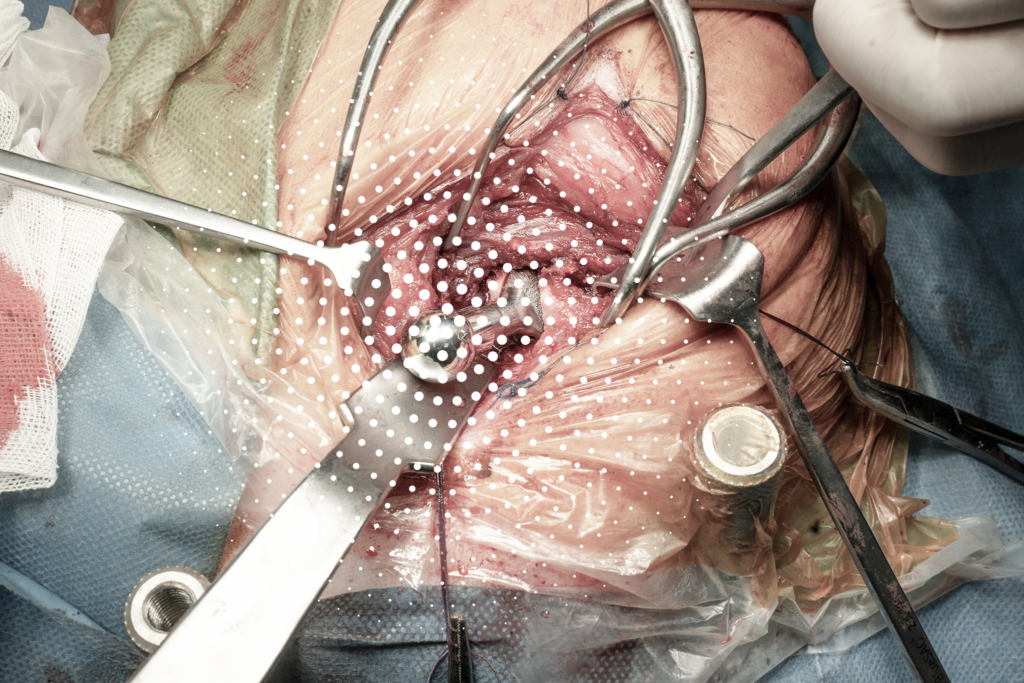

Quá trình thay khớp háng cho chó diễn ra với sự chính xác tuyệt đối:

- Sky được đặt vào thiết bị cố định vùng xương chậu để giữ vững tư thế.

- Các phần xương và sụn bị tổn thương được bác sĩ cắt bỏ cẩn thận.

- Chỏm xương đùi hỏng được thay thế bằng chỏm xương đùi nhân tạo, sau đó gắn chính xác vào phần ổ cối nhân tạo.

- Sự lắp ghép này tạo ra một khớp háng mới vừa vững chắc, vừa linh hoạt.

Ca phẫu thuật được hiện thực hóa nhờ sự hỗ trợ của bộ dụng cụ chuyên biệt từ BlueSAO – mang lại công nghệ hiện đại, độ an toàn sinh học và độ bền cao cho thú cưng.